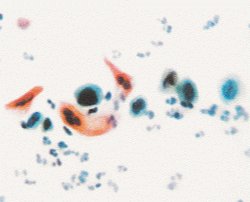

6.鳞状细胞癌(SCC)

结果解读:细胞大小和形态明显异常,提示宫颈已有癌变。

处理原则:立即行阴道镜检查+宫颈活检,根据病变程度进行手术或其他治疗。